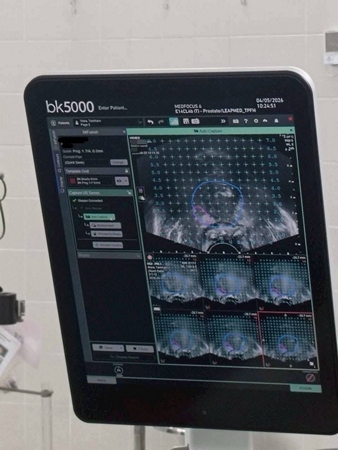

ร.พ.สมเด็จพระนางเจ้าสิริกิติ์ กรมแพทย์ทหารเริอ อ.สัตหีบ จ.ชลบุรี ได้ดำเนินการรักษาผู้ป่วยด้วยเทคนิค IRE (Irreversible Electroporation) Focal Prostate Therapy เป็นรายแรก สำเร็จลุล่วง เมื่อวันที่ 5 เม.ย.69 นับเป็นอีกหนึ่งความก้าวหน้าทางการแพทย์ที่มุ่งเน้นการรักษาแบบจำเพาะจุด (Focal Therapy) เพื่อลดผลกระทบต่อเนื้อเยื่อข้างเคียง และคงคุณภาพชีวิตของผู้ป่วยให้ได้มากที่สุด

IRE เป็นนวัตกรรมการรักษาที่ใช้กระแสไฟฟ้าความเข้มสูงในการทำลายเซลล์มะเร็งเฉพาะบริเวณเป้าหมาย โดยไม่ก่อให้เกิดความร้อนสูง จึงช่วยลดความเสียหายต่อโครงสร้างสำคัญ เช่น เส้นประสาทและหลอดเลือดบริเวณรอบข้าง ส่งผลให้ลดภาวะแทรกซ้อน เช่น ภาวะกลั้นปัสสาวะไม่ได้

ความสำเร็จนี้ เกิดจากความร่วมมือของทีมสหสาขาวิชาชีพ ทั้งศัลยแพทย์ วิสัญญีแพทย์ พยาบาลห้องผ่าตัด และบุคลากรที่เกี่ยวข้องทุกฝ่าย ภายใต้มาตรฐานความปลอดภัยสูงสุด